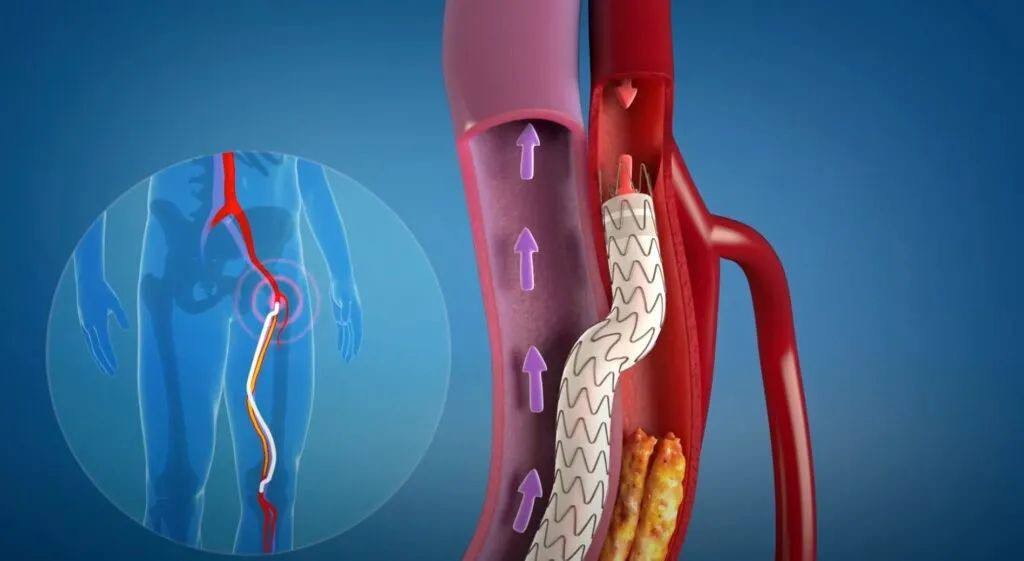

外周静脉取栓支架

项目类型

器械质押区

起投金额

200USDT

每日释放:1

释放周期:97 天

已购: 150000

剩余: 0